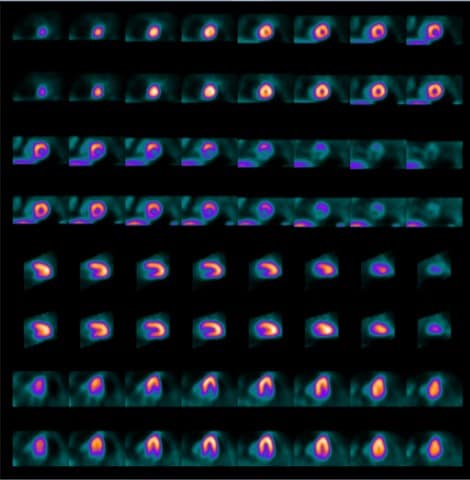

Imagistica perfuziei miocardice 4 min stres / 6 min repaus